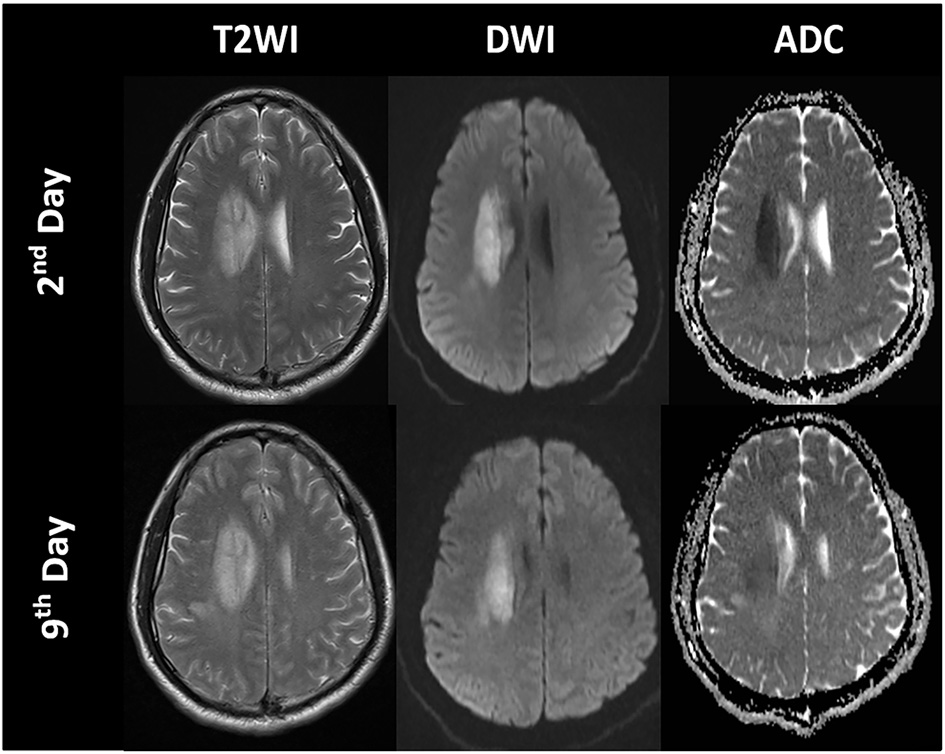

Diffusion MRI is sensitive to the diffusion of water molecules in biological tissue and plays a critical role in the research and clinical management of acute stroke. Diffusion-weighted imaging (DWI) is the most frequently used technique to detect cytotoxic edema. An increase in DWI and a decrease in apparent diffusion coefficient (ADC) can be observed several hours after acute ischemia because of extracellular fluid loss and swelling of various cellular compartments, which are proportionate to the degree of intracellular water accumulation (60, 61). ADC declines immediately when the cerebral blood flow (CBF) falls below 20 to 40 ml/100 g/min in animals and humans (22), and the most dominant decay occurs within the first hours (1–1.5 h) (57, 61, 62). Subsequently, ADC values increase in the days following stroke because of progressive ionic and vasogenic edema and cell lysis, which results in a phenomenon called ADC pseudo-normalization (63) (Figures 4, 5). Therefore, timely imaging (24–48 h after stroke onset) is essential to evaluate the process of cytotoxic edema.

Figure 4

Time course of the signal intensities in T2-weighted imaging (T2WI), diffusion-weighted imaging (DWI), and apparent diffusion coefficient (ADC) maps of a patient with a right paraventricular infarct.

Figure 5

Cytotoxic edema, ionic edema, and vasogenic edema on MRI and CT. A 69-year-old male underwent MRI and CT on day 5 post-stroke. (A) DWI shows hyperintensity in the left frontal and parietal lobes. (B) ADC map shows hypointensity in the marginal area of the lesion, indicating cytotoxic edema, and hyperintensity in the lesion center, indicating ionic and vasogenic edema. (C) CT image shows hypodensity in the left frontal and parietal lobes, especially in the area of ionic and vasogenic edema (i.e., ADC hyperintensity area).